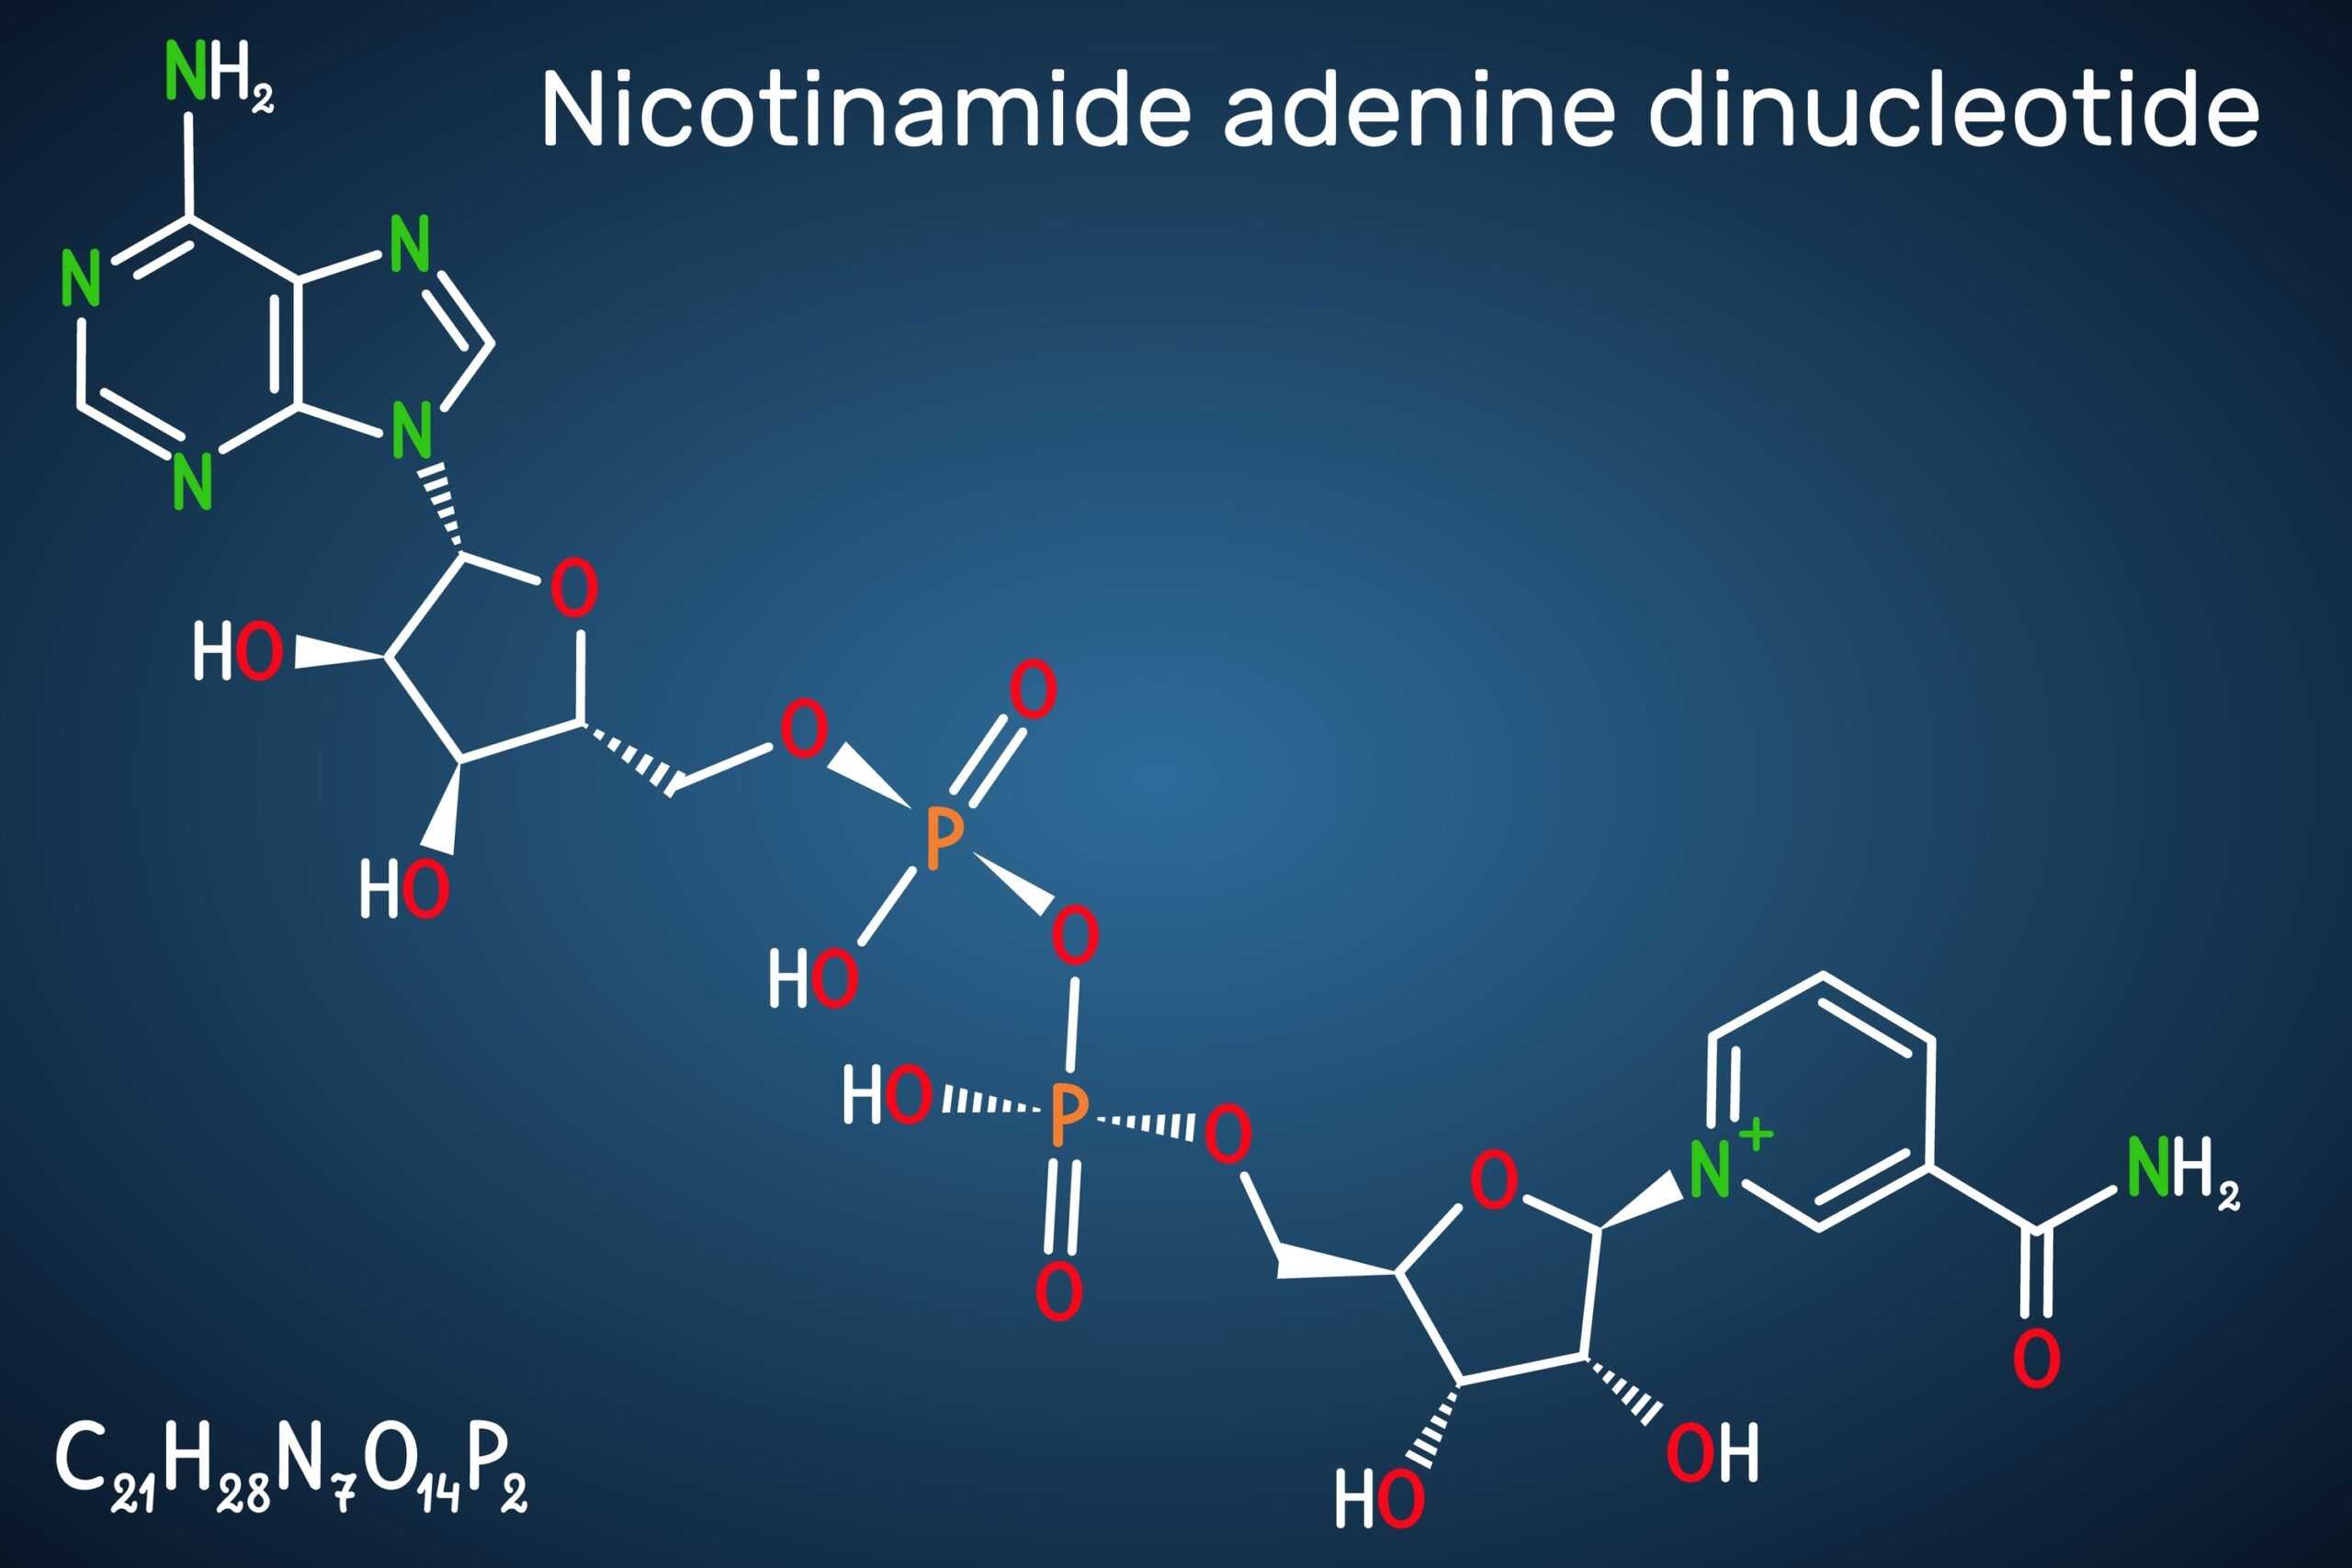

NAD

NAD (Nicotinamide Adenine Dinucleotide) is not composed of amino acids. Instead, it is a coenzyme made up of two nucleotides joined through their phosphate groups. Each nucleotide consists of a different base:

- Adenine: A purine base.

- Nicotinamide: A derivative of vitamin B3 (niacin).

The structure of NAD includes:

- Adenosine Monophosphate (AMP): Consisting of adenine, ribose, and a phosphate group.

- Nicotinamide Mononucleotide (NMN): Consisting of nicotinamide, ribose, and a phosphate group.